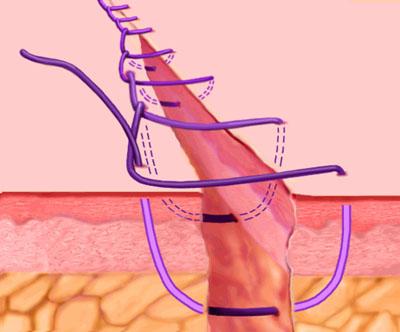

این نوع بخیه تحت نام بخیه ممتد یا همان continuous هم در بخش بالینی ما شناخته شده است شکل کاملا واضح است اما اگر باز هم مشکلی بود پیغام بگذارید تا توضیح کامل فارسی بگذارم.

Running, or Continuous Stitch

The "Running" stitch is made with one continuous length of suture material. Used to close tissue layers which require close approximation, such as the peritoneum. May also be used in skin or blood vessels. The advantages of the running stitch are speed of execution, and accommodation of edema during the wound healing process. However, there is a greater potential for malapproximation of wound edges with the running stitch than with the interrupted stitch

Continuous Locking, or Blanket Stitch

A self-locking running stitch used primarily for approximating skin edges